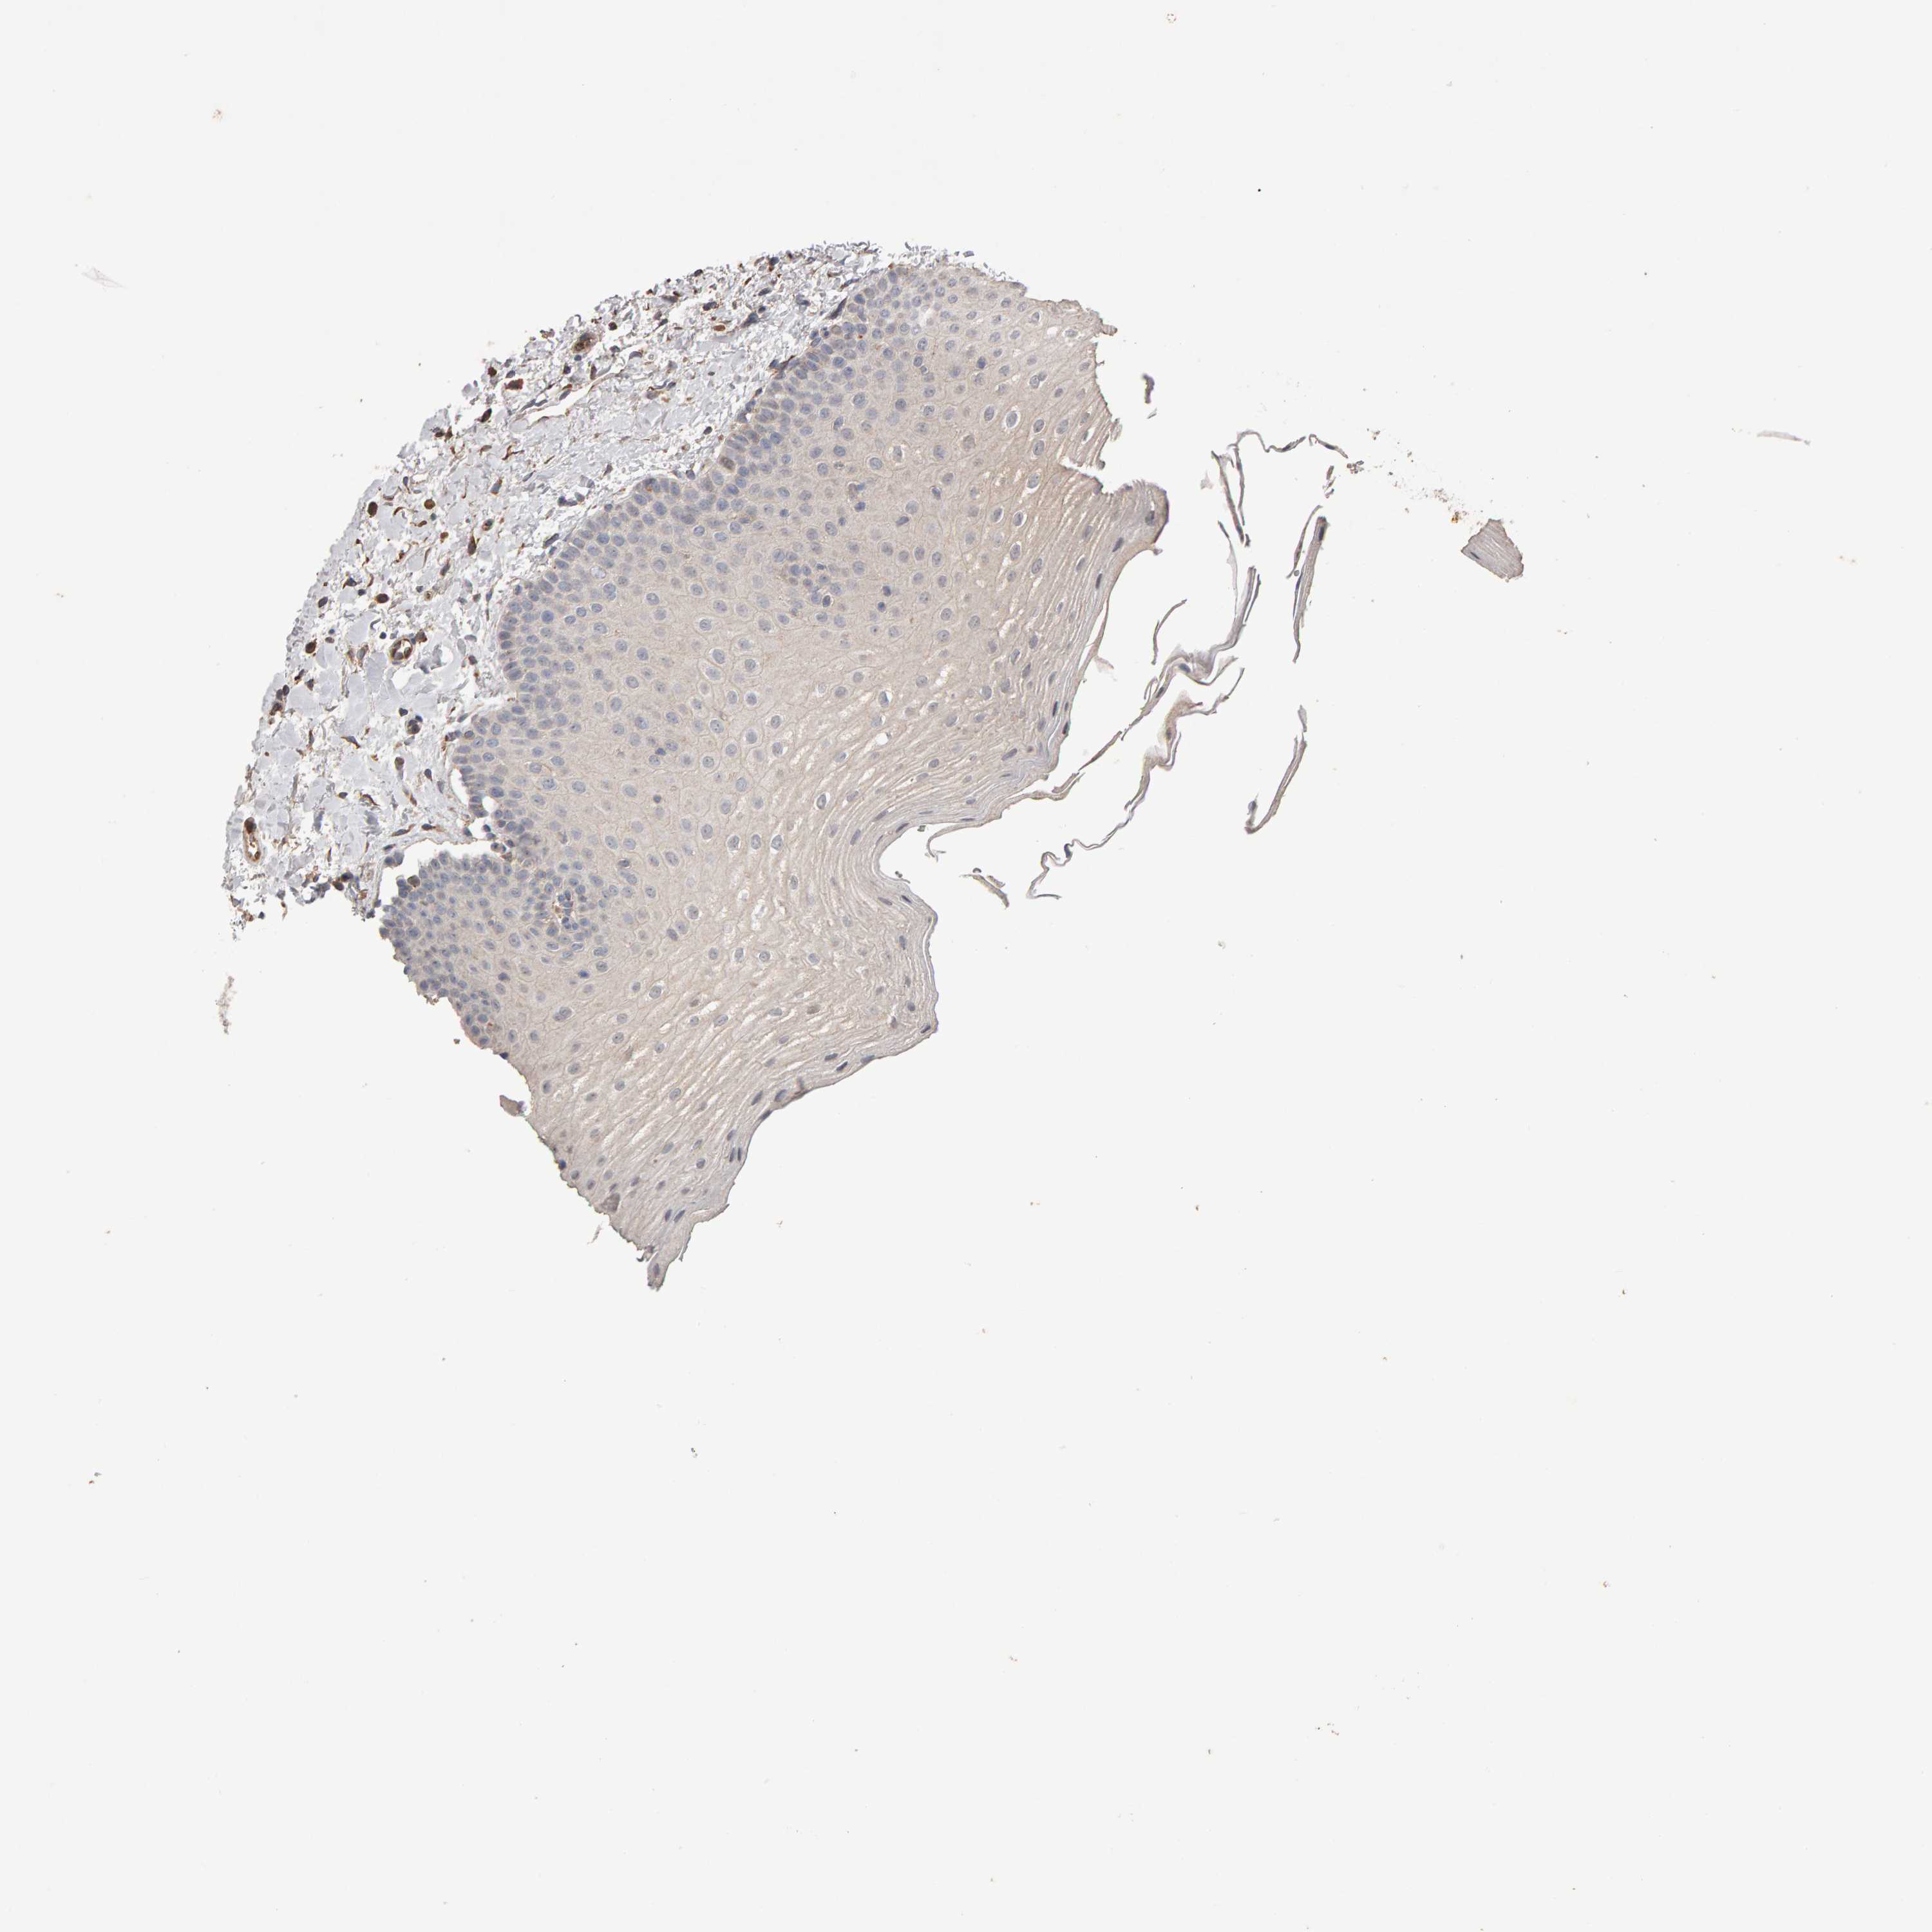

TISSUE PRIMARY DATA ORAL MUCOSA Show tissue menu

ORAL MUCOSA - Antibody stainingi

Antibody staining in the annotated cell types in the current human tissue is reported as not detected, low, medium, or high, based on conventional immunohistochemistry profiling in selected tissues. This score is based on the combination of the staining intensity and fraction of stained cells.

Each image is clickable and will lead to virtual microscopy that enables deeper exploration of all samples and also displays staining intensity scores, fraction scores and subcellular localization as well as patient and tissue information for each sample.

Antibody HPA022875Antibody HPA022912Antibody HPA023273

Squamous epithelial cells MediumNot detectedLow